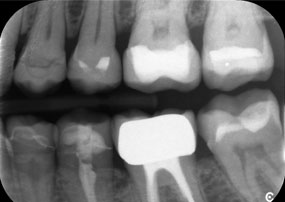

The challenge was to remove twelve splinted crowns made of a base metal alloy without damaging the underlying abutment teeth. The handpiece was used to precisely section the ceramic layers and divide the metal framework using a carbide bur, enabling minimally traumatic crown removal. Within just 30 minutes, the old restorations were removed, allowing for the preparation of a new prosthesis, comprising full-contour zirconia in the posterior region and veneered crowns anteriorly. The result was a complete restoration that delivered both functional and aesthetic success (see Fig. 1).

A jaw x-ray from an 81-year-old patient, in front of a black background.

Figure 1: Aesthetic rehabilitation of PFM crowns: Complete removal and replacement of 40-year-old PFM crowns to improve aesthetics in an 81-year-old patient.